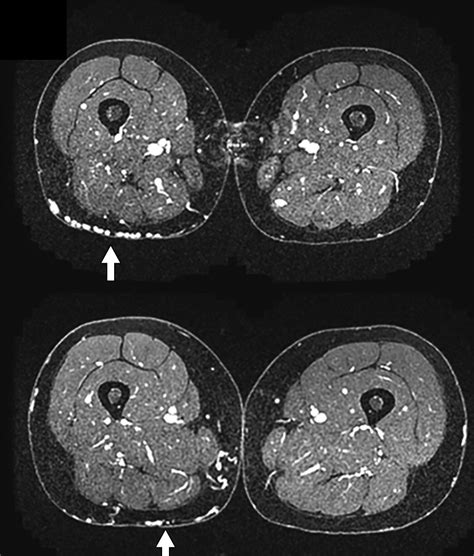

• Swelling: Swelling in the legs, vulva, or rectum.

• Varicose veins: Visible varicose veins in the pelvic area, vulva, or legs.

• Imaging tests: Various imaging tests may be used to visualize the veins and assess blood flow. These tests include:

Computed Tomography Venography (CTV) Uses CT scans to visualize the veins after injecting a contrast dye.